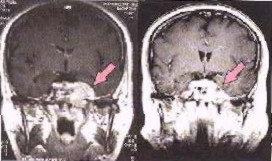

Image left: A brain lesion is clearly localised by a SPECT scan (left). The glioma (a type a brain tumor) is poorly defined in the X ray tomography (right) but can be seen as a clear dark spot on a SPECT image done with Tc-99m.

There are many applications of SPECT both in and as a therapy aid. SPECT scans using a radioisotope not absorbed by tissues but instead travelling in the bloodstream can be used to see how blood flows to certain tissues and organs. This is particularly useful for scans of the brain and heart.